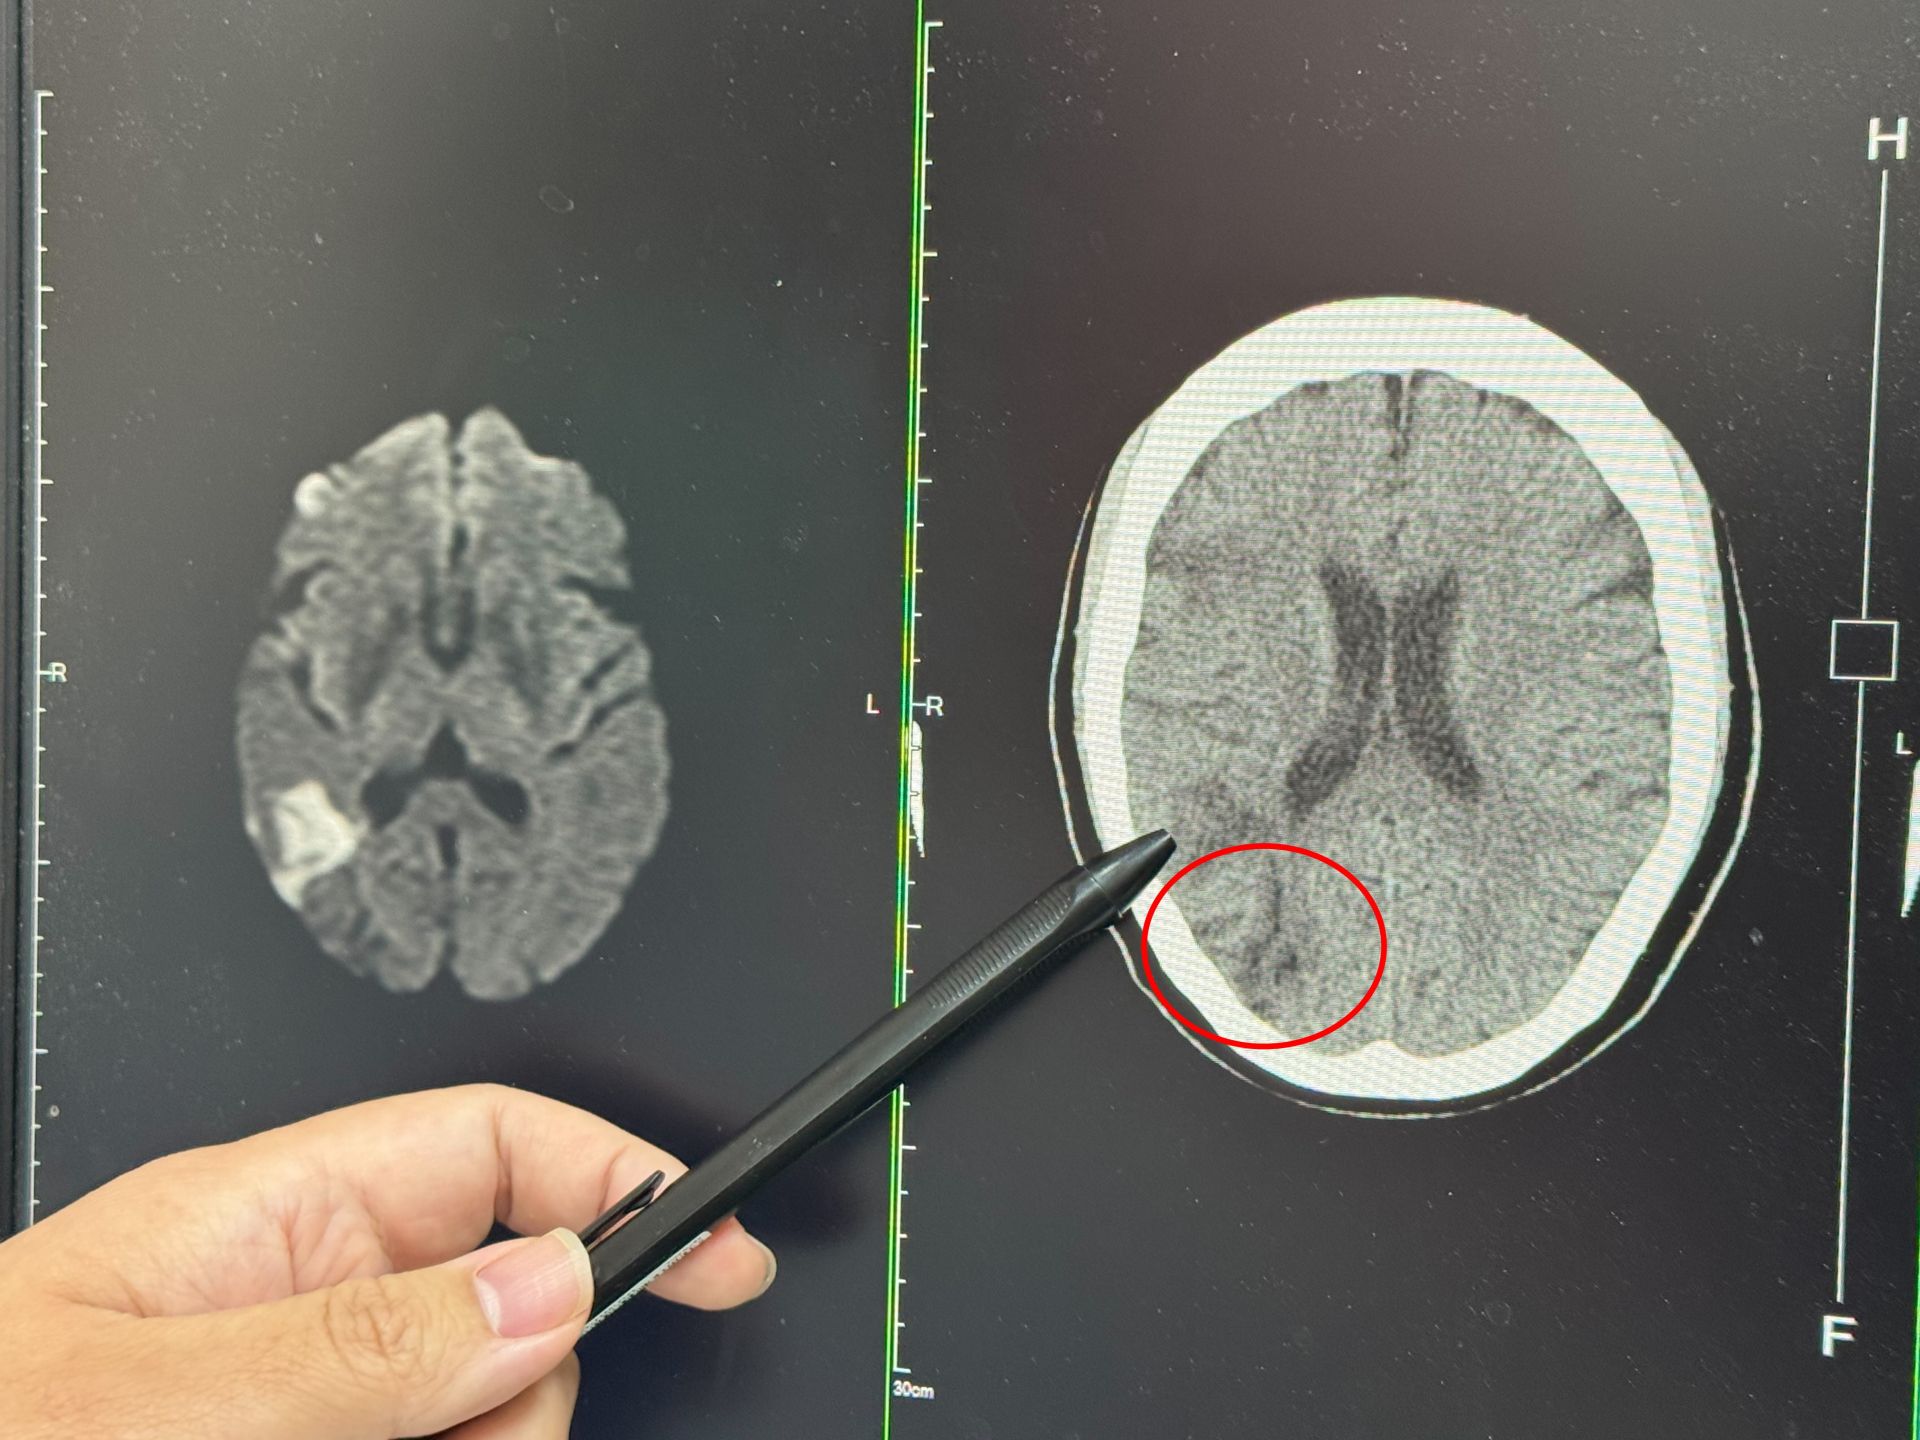

李綜合醫院神經內科醫師張峻誠說,一名婦人右側中大腦動脈阻塞而影響到視野

一名婦人右側中大腦動脈阻塞而影響到視野。大甲李綜合提供

張峻誠說,聽完患者的描述,研判此症狀即是中風,先安排電腦斷層檢查,果然看到右邊中大腦動脈阻塞,為了確認阻塞範圍,進一步做核磁共振,詳細判讀後發現,婦人當時眼睛出現模糊時已經初次中風,只是比較幸運範圍較小,沒有出現手腳無力、無法行走的情形。